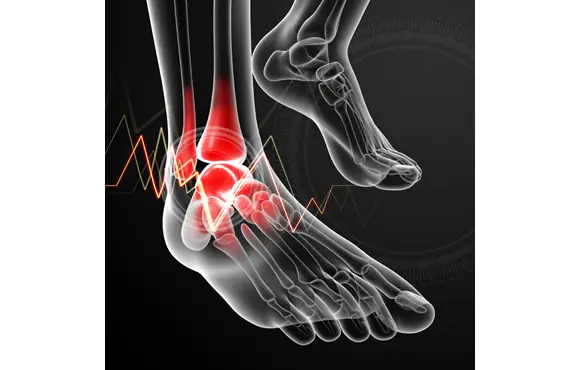

A study published in the Journal of Orthopedic and Sports Physical Therapy found that subjects with tight calves were 4.6 times more likely to sustain a metatarsal stress fracture. Studies show that a common cause of stress fractures is calf tightness, which causes a premature lifting of the heel while running and transfers a significant amount of force into the forefoot. The soldiers were exempted from duty for an average of 26.5 days in order to recover fully. In the study, 191 cases with 204 fractures were analyzed, and more than 50 percent of the fractures occurred within the first eight weeks of service. Recruits for the German Armed Forces in the years from 1998–2000 participated in a study examining stress fracture rates. This theory is supported by evidence that military recruits are most likely to endure a stress fracture during their first weeks of service. If you’re new to running, read up on running tips for beginners in order to avoid an injury. Shoot for no more than a 10 percent increase in load per week in order to strengthen your muscles and avoid overtraining. Therefore, you need to gradually intensify your training or workouts so your bones can properly adapt to the added stress. When you increase intensity, your bone is actually weaker for about a month after the change before it becomes stronger. Intensify Training Slowlyĭon’t make drastic changes in milage or intensity when training. If you take some precautions, you can avoid a stress fracture, and that’s key because a stress fracture keeps you on the couch for six to eight weeks while you wait for your bones to recover.Ĩ Ways to Avoid a Stress Fracture 1. That’s why it’s important to increase training intensity gradually, instead of increasing mileage or weight before the bone has a chance to rest and repair. The pain is similar shin splints or a heel spur and oftentimes can even be confused for them at first, but a stress fracture is even more common and more problematic if left untreated.ĭid you know that a bone continuously remodels itself to withstand the stress involved with physical activity? But stress fractures occur with increased remodeling, causing a weakening of the outer surface of the bone. The repeated stress is lower than the stress required to fracture the bone in a single event, but over time it will do damage. The fatigued muscle eventually transfers the stress to the bone, which causes tiny cracks or stress fractures.

Eventually, that stress can lead to a stress fracture.Ī stress fracture occurs when muscles become fatigued and can’t handle added shock. In fact, in running sports they may account for up to 30 percent of all injuries. That’s because our bones endure stress whenever a force is loaded upon it, whether the stress comes from the pull of a muscle or the shock of a leg or foot contacting the ground, there is stress put on the load-bearing bone. Stress fractures account for over 10 percent of all injuries in sports medicine clinics, and they’re some of the most common running injuries there are.